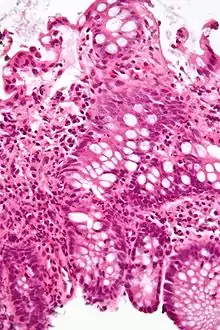

Micrograph of the small intestine mucosa showing the intestinal glands - bottom 1/3 of image. H&E stain.

In histology, an intestinal gland (also crypt of Lieberkühn and intestinal crypt) is a gland found in between villi in the intestinal epithelium lining of the small intestine and large intestine (or colon). The glands and intestinal villi are covered by epithelium, which contains multiple types of cells: enterocytes (absorbing water and electrolytes), goblet cells (secreting mucus), enteroendocrine cells (secreting hormones), cup cells, tuft cells, and at the base of the gland, Paneth cells (secreting anti-microbial peptides) and stem cells.

Intestinal glands are found in the epithelia of the small intestine, namely the duodenum, jejunum, and ileum, and in the large intestine (colon), where they are sometimes called colonic crypts. Intestinal glands of the small intestine contain a base of replicating stem cells, Paneth cells of the innate immune system, and goblet cells, which produce mucus.[1] In the colon, crypts do not have Paneth cells.[2]